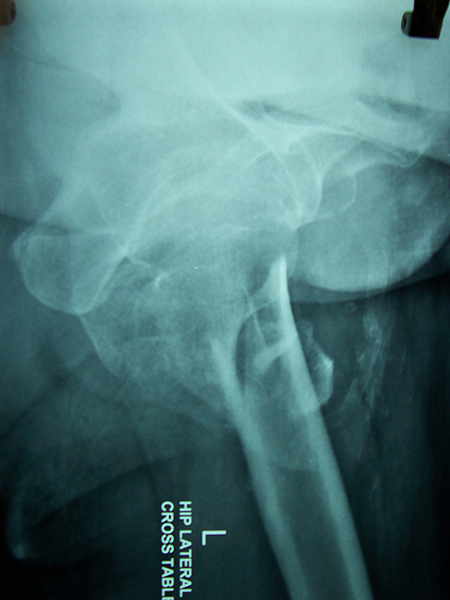

Case:7 Fracture Neck Femur with Implant failure and Re-Fixation with hemi-arthroplasty

Alcoholic Gardener by profession had slipped in bathroom & fell. He sustained fracture neck femur.He was operated with closed reduction & CC Screw fixation under IITV. Two weeks’ post fixation he again fell & sustained fracture in sub trochanteric region. He was treated with Hem-Arthroplasty with Tension band wiring.

Pre-Op

Post-Op

Post Fall

Oblique-Post Fall

Lat-Post Fall